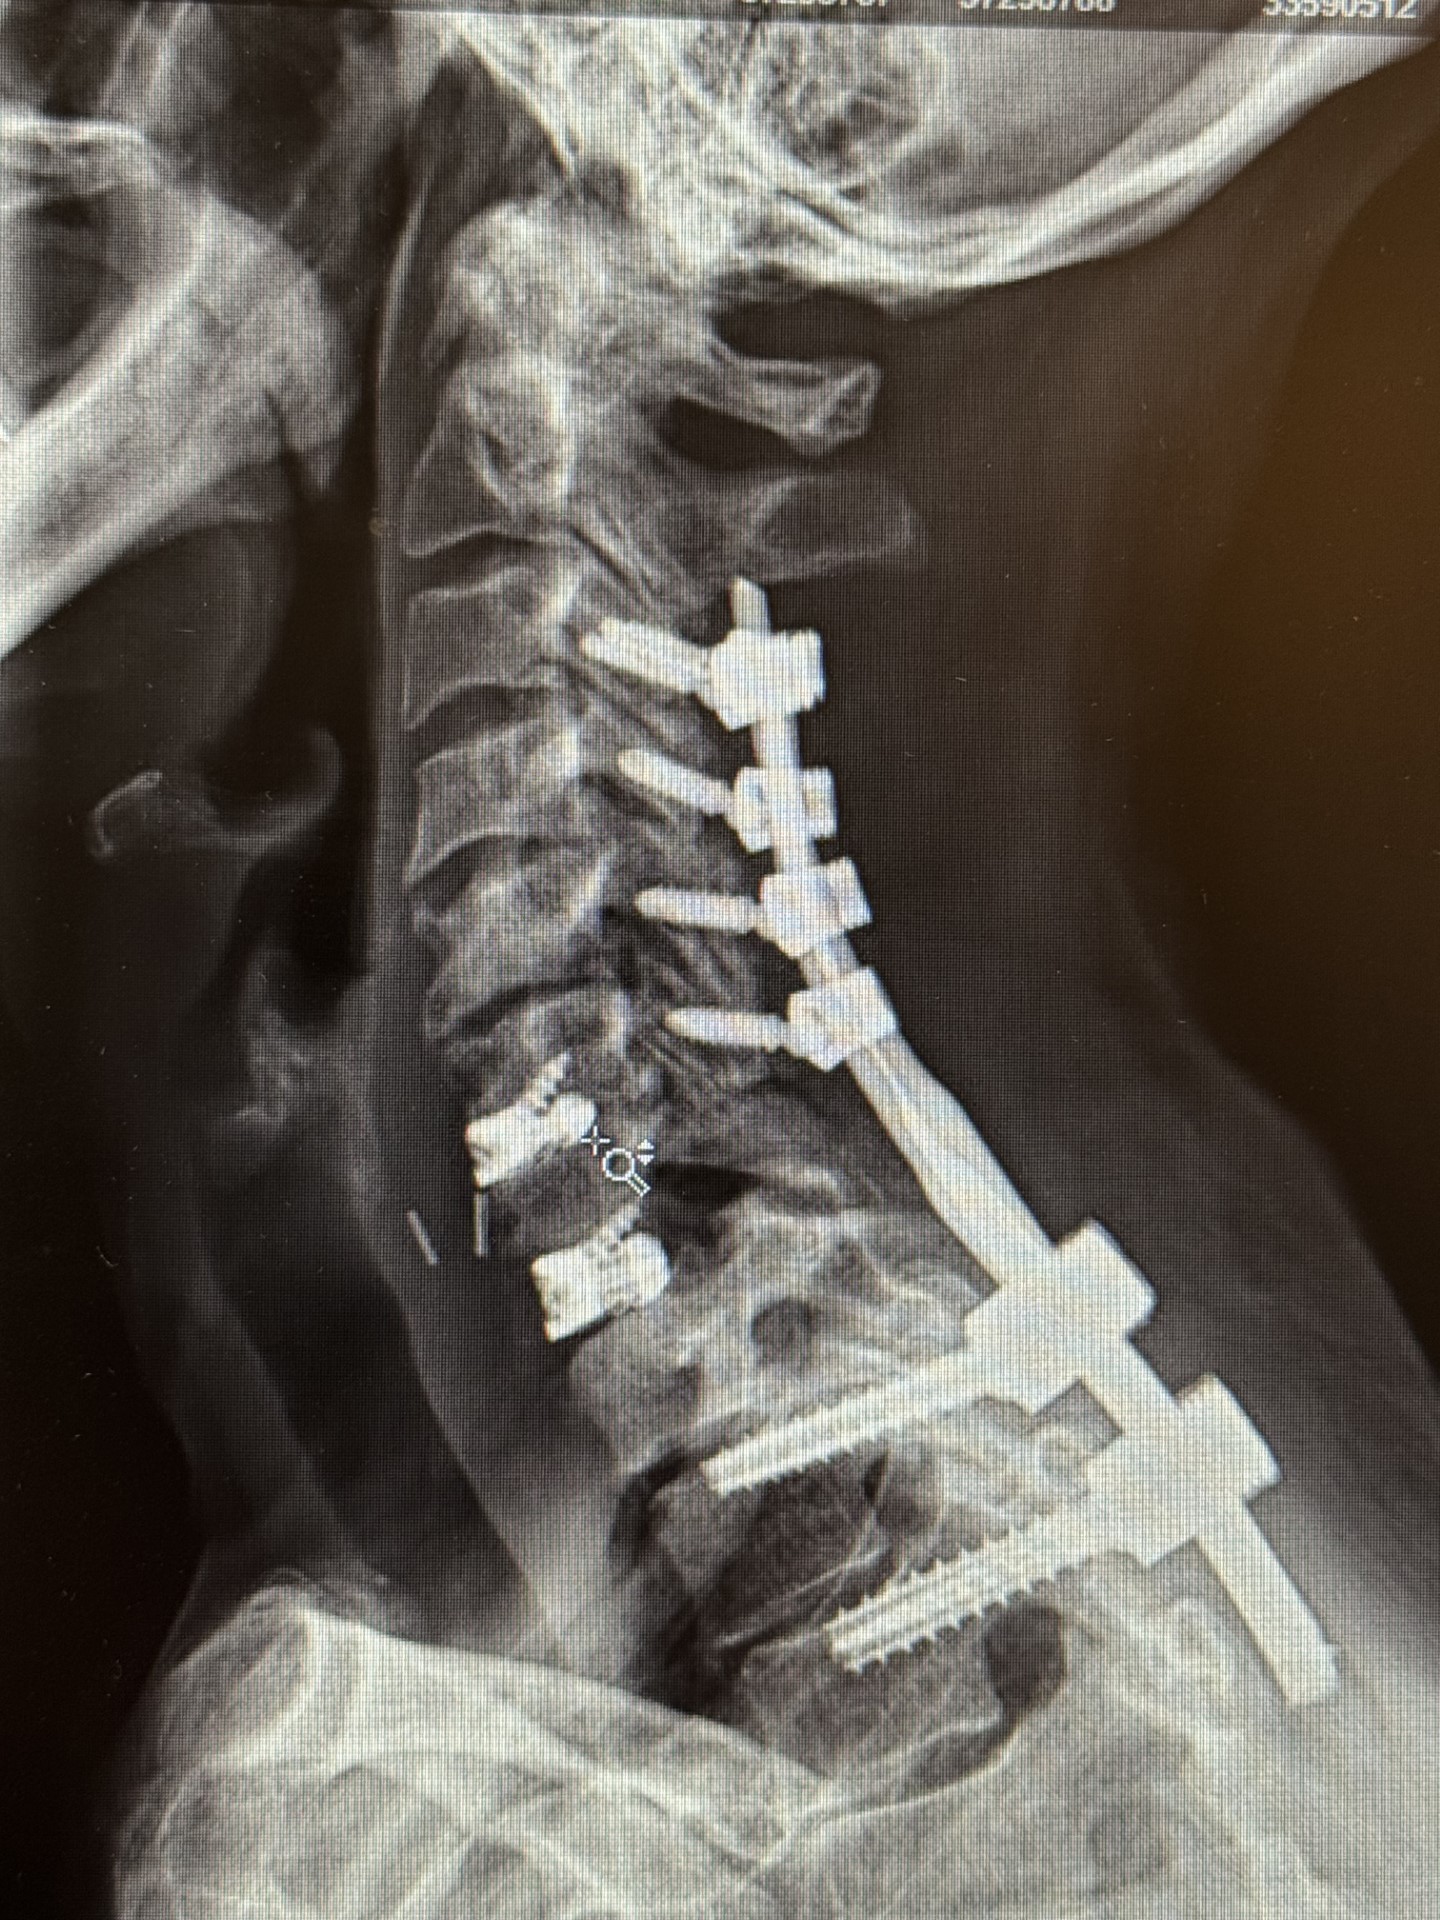

Minimally Invasive Spine Surgery Treats Acute Leg and Foot Weakness